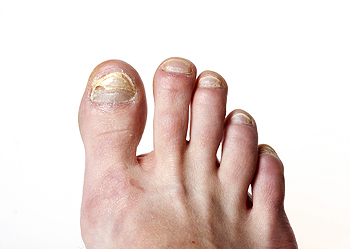

Onychomycosis, a fungal infection of the nail that leads to thickening, discoloration, and brittle changes, is being approached with greater accuracy and more individualized care. Evaluation often includes lab testing, such as nail sampling with a microscopic evaluation or culture to confirm fungus before care begins, helping to avoid unnecessary or ineffective medications. Care options have also expanded beyond standard oral medications. Newer topical treatments are designed to better reach the nail bed, improving results for some patients. In certain cases, combining methods may offer better outcomes and lower the chance of recurrence. Daily foot care, keeping nails trimmed, and choosing breathable footwear all support long-term nail health. When nail changes persist or worsen despite home care, it is suggested that you see a podiatrist who can guide you toward the most appropriate next steps.

If left untreated, toenail fungus may spread to other toenails, skin, or even fingernails. If you suspect you have toenail fungus it is important to seek treatment right away. For more information about treatment, contact one of our podiatrists of Active Foot and Ankle Care, LLC. Our doctors can provide the care you need to keep you pain-free and on your feet.

If self-care strategies and over-the-counter medications does not help your fungus, your podiatrist may give you a prescription drug instead. Even if you find relief from your toenail fungus symptoms, you may experience a repeat infection in the future.

In order to prevent getting toenail fungus in the future, you should always make sure to wash your feet with soap and water. After washing, it is important to dry your feet thoroughly especially in between the toes. When trimming your toenails, be sure to trim straight across instead of in a rounded shape. It is crucial not to cover up discolored nails with nail polish because that will prevent your nail from being able to “breathe”.

In some cases, surgical procedure may be needed to remove the toenail fungus. Consult with your podiatrist about the best treatment options for your case of toenail fungus.